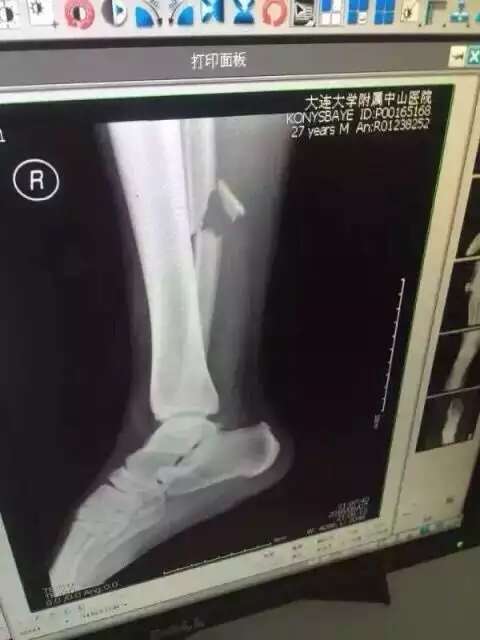

Инцидент случился на 45-й минуте матча, который проходил в Даляне. За него Хан получил предупреждение, а Конысбаев в результате инцидента получил ужасную травму. Прямо с поля полузащитник был увезен на машине "скорой помощи" в больницу, где ему сделали операцию.

Фото со страницы пользователя Facebook Сержана Касена